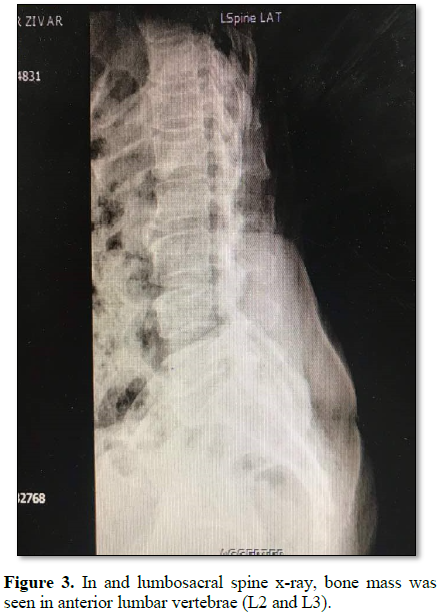

The patient was a 40 year old woman suffering from chronic neck pain and dysphagia and shortness of breath. She was under investigation and imaging to diagnose digestive and respiratory diseases and pharyngeal disease that was healthy. But in the lateral cervical x-ray, a bone mass adhered to the anterior cervical vertebra was observed (Figure 1). This patient was not obese (BMI=18.5) had no history of any rheumatoid, cardiovascular and metabolic disease and there was no evidence of disease in the studies. She did not have any neurological and motor disorder and sphincteric disorder. In the lateral cervical x-ray, a large calcified anterior ligamentous mass was observed in anterior part of body of C4, C5 and C6 vertebrae (Figure 1), causing partial obstruction of esophagus. In cervical MRI, in T1 view, isointense to hyperintense mass were observed on the anterior C4, C5, C6 and in T2 view, heterogeneous and isointense to hypointense mass was observed in the anterior cervical vertebrae (Figure 2). In thoracic spine and lumbosacral spine x-ray, bone mass was seen in anterior lumbar vertebrae (L2 and L3) (Figure 3), which had not caused any symptoms in the patient. This patient was underwent surgery and the anterior neck calcification was removed (Figure 4) and after a few days symptoms of dysphagia and dyspnea were resolved.